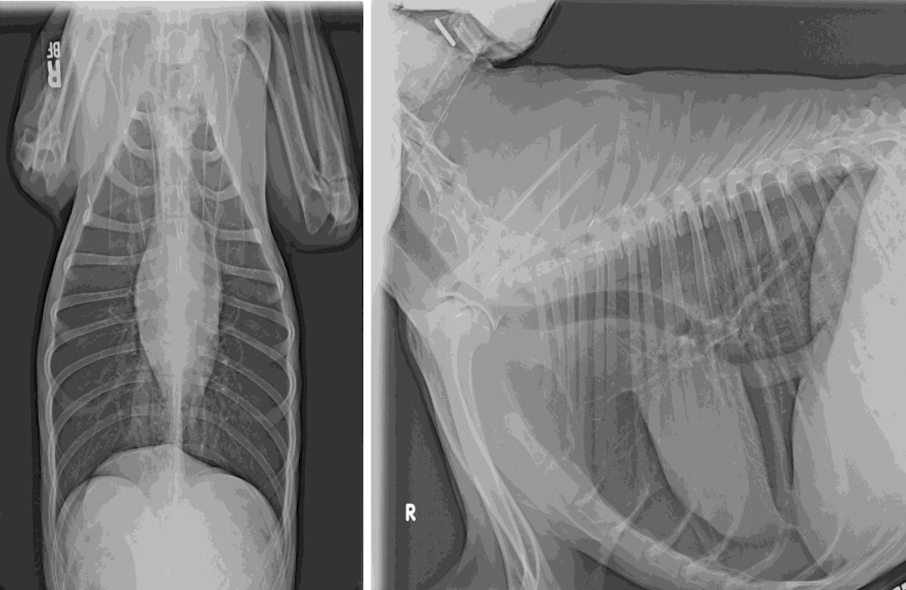

What condition?

Atelectasis secondary to pneumothorax

note: retraction of lung lobes from thoracic wall and soft tissue opacity of left and right middle lung lobe